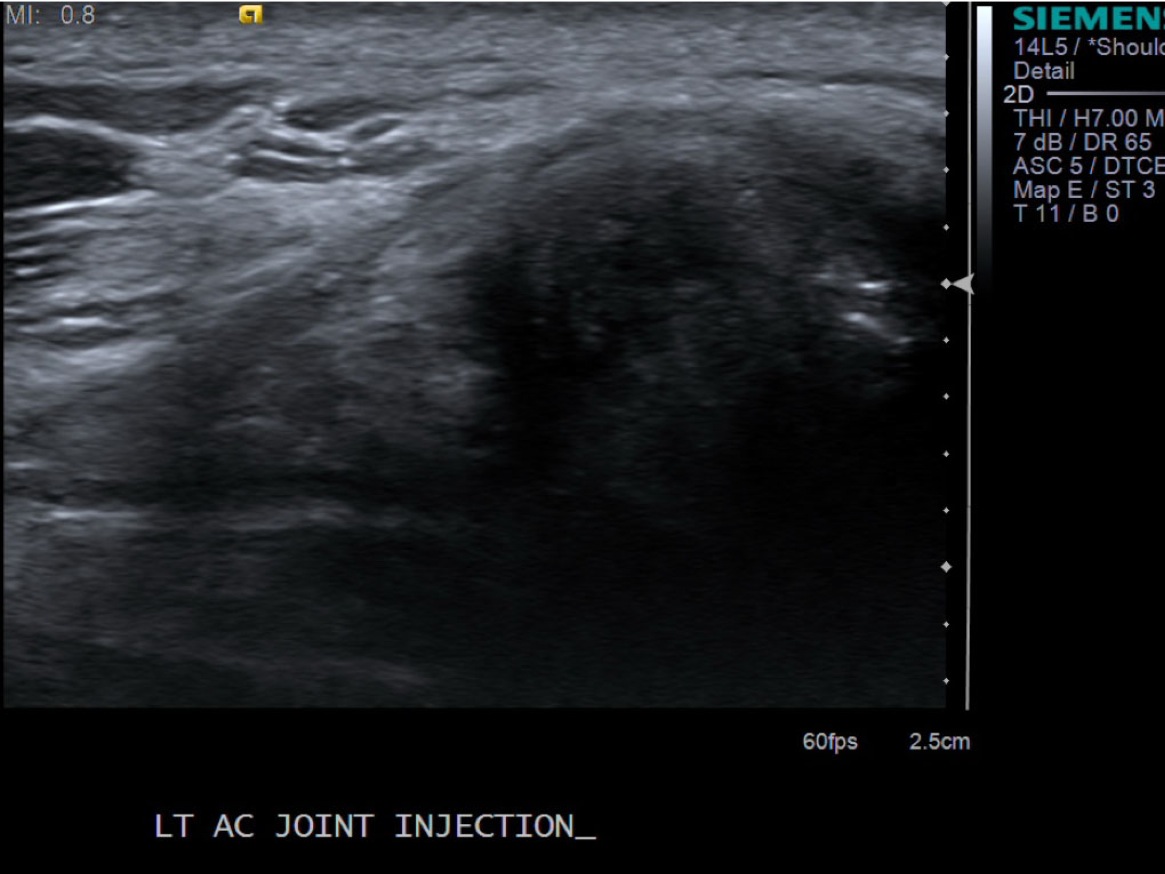

7. Under ultrasound guidance, advance needle into the AC joint. Test inject with 1% lidocaine. If no resistance, switch 1% lidocaine for injectable steroid mixture. If there is resistance, reposition needle and test inject again. Inject 0.5 -1 cc of injectable steroid/anesthetic mixture.

• descriptiondescription

8. Pull needle out and follow standard post-procedure protocol with cleaning off the skin and placing a bandage. Post procedure transverse images demonstrating distention of the joint with steroid and anesthetic.